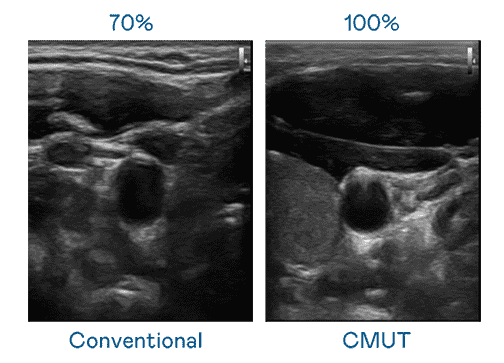

CMUT 技术是一种用电容式微机电元件来产生超音波讯号的技术。。。与传统 PZT 压电式技术相比,,,CMUT 频宽增加 30%,,,更宽频的超音波讯号让影像解析度大幅提升,,是实现高影像品质医疗超音波扫描、、、、促进精准医疗发展的关键技术。。

大频宽带来超清晰影像

超音波影像的解析度高低,,,,首先取决于探头能发出的讯号频宽。。。william威廉中文官网 CMUT 可提供高清晰的超音波讯号,,提供高频宽、、、、高灵敏度、、、、影像纹理细节更高的超音波影像,,协助医护人员缩短影像判读时间及利用精准的医疗影像进行诊断。。